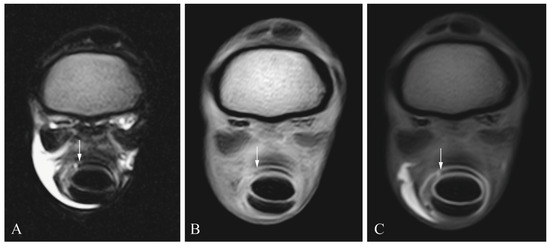

2.3. Diagnostic Imaging

2.4. Image Analysis